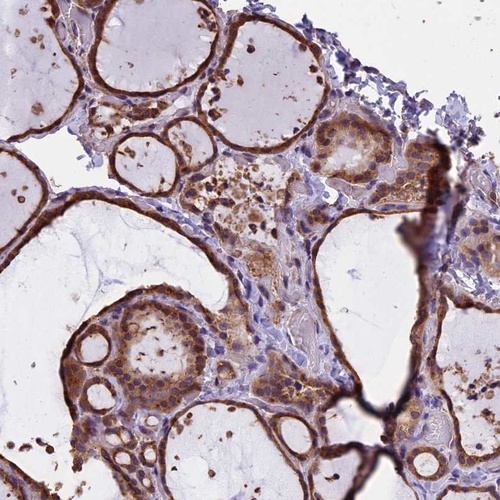

Immunohistochemistry analysis in human thyroid gland and pancreas tissues using Anti-CHMP2A antibody. Corresponding CHMP2A RNA-seq data are presented for the same tissues.